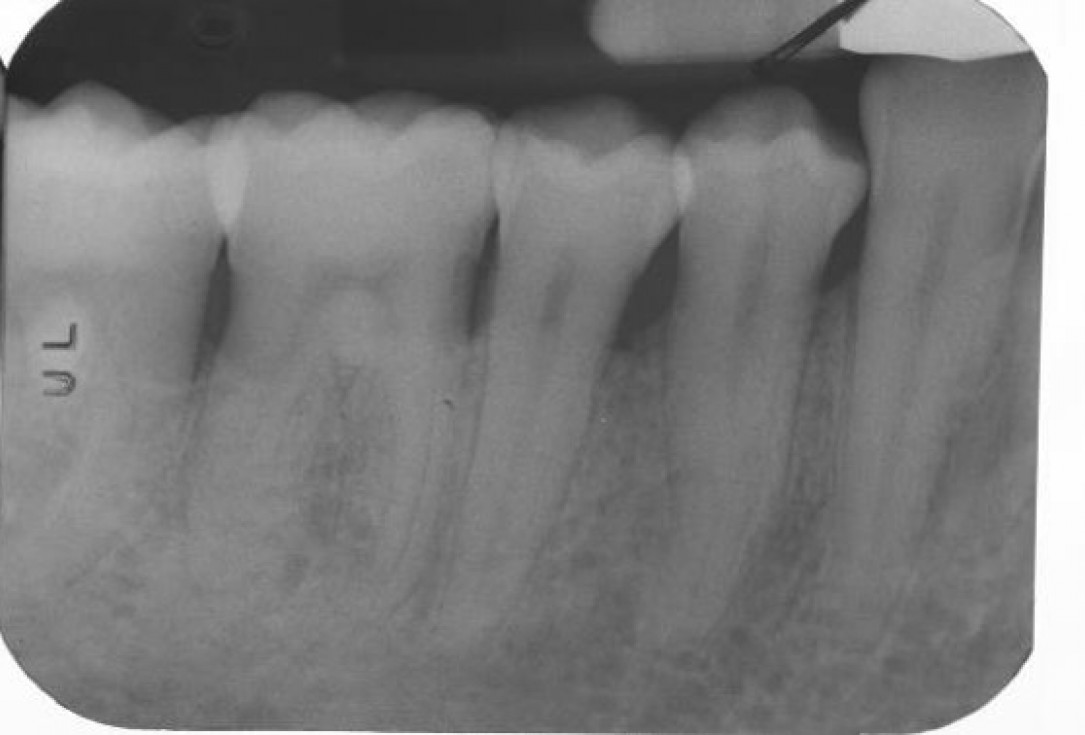

03/22 - Pre-operative radiograph. Deep intrabony defect visible on the distal aspect of tooth 46.

Deep intrabony defects treated using Straumann® Emdogain® - Dr. M. Stefanini